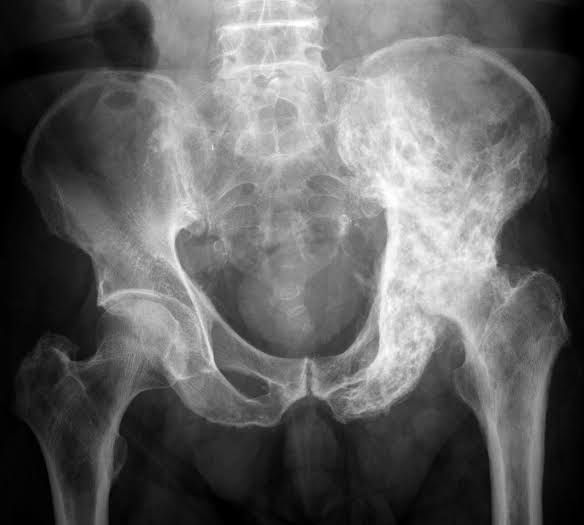

Paget's (PAJ-its) disease of bone interferes with your body's normal recycling process, in which new bone tissue gradually replaces old bone tissue. Over time, bones can become fragile and misshapen. The pelvis, skull, spine and legs are most commonly affected.